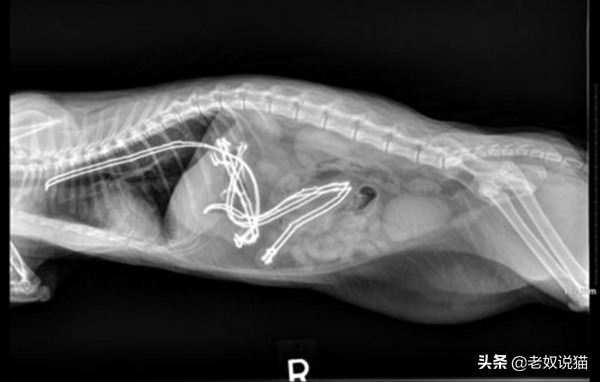

美国一只叫Winnie的猫误食46根发圈